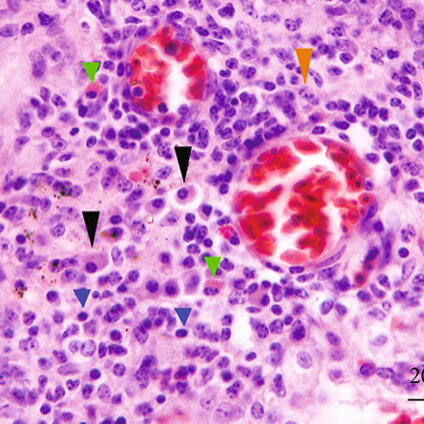

Detecting Mycoplasma columbinasale in Pigeon Respiratory Disease